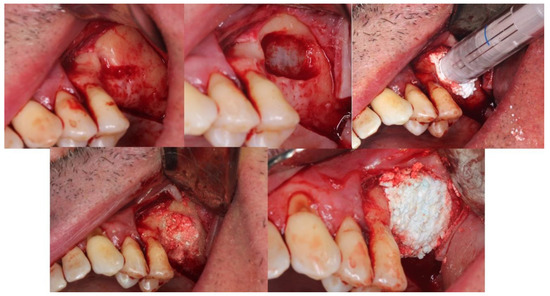

4.1. Patient No. 1

| 1 F 63 | NO [Tobacco: 2 cig/day] Horizontal Guided Bone Regeneration | Yes [No] | G | No | G | No | No |